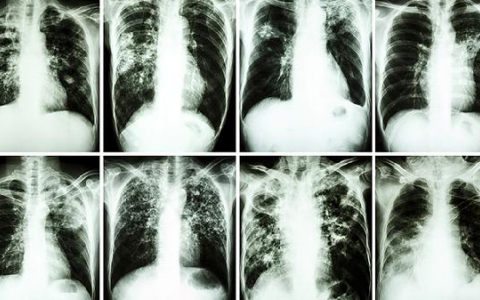

肺部

肺部结节在医学影像中是一个常见的发现,尤其在老年人中更为普遍。这种结节通常是直径小于3厘米的阴影,虽然大多数是良性的,但也可能与肺癌等严重疾病相关。预防肺部结节

肺部结节的良恶性判断并不是简单通过影像学检查就能确定的。通常需要结合患者的临床表现、体征以及病理组织活检等多方面的信息进行综合分析。简单来说,影像学检查只是初步